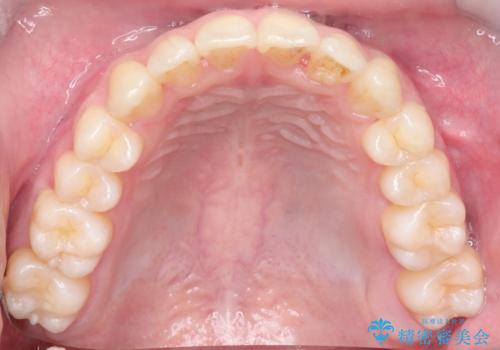

【クリア装置】前歯の凸凹を綺麗にしたい

- 前歯の凸凹を主訴に来院されました。

マウスピース矯正も適応でしたが、ワイヤー矯正を希望され治療を行なっております

治療期間も短く大変満足していただきました。